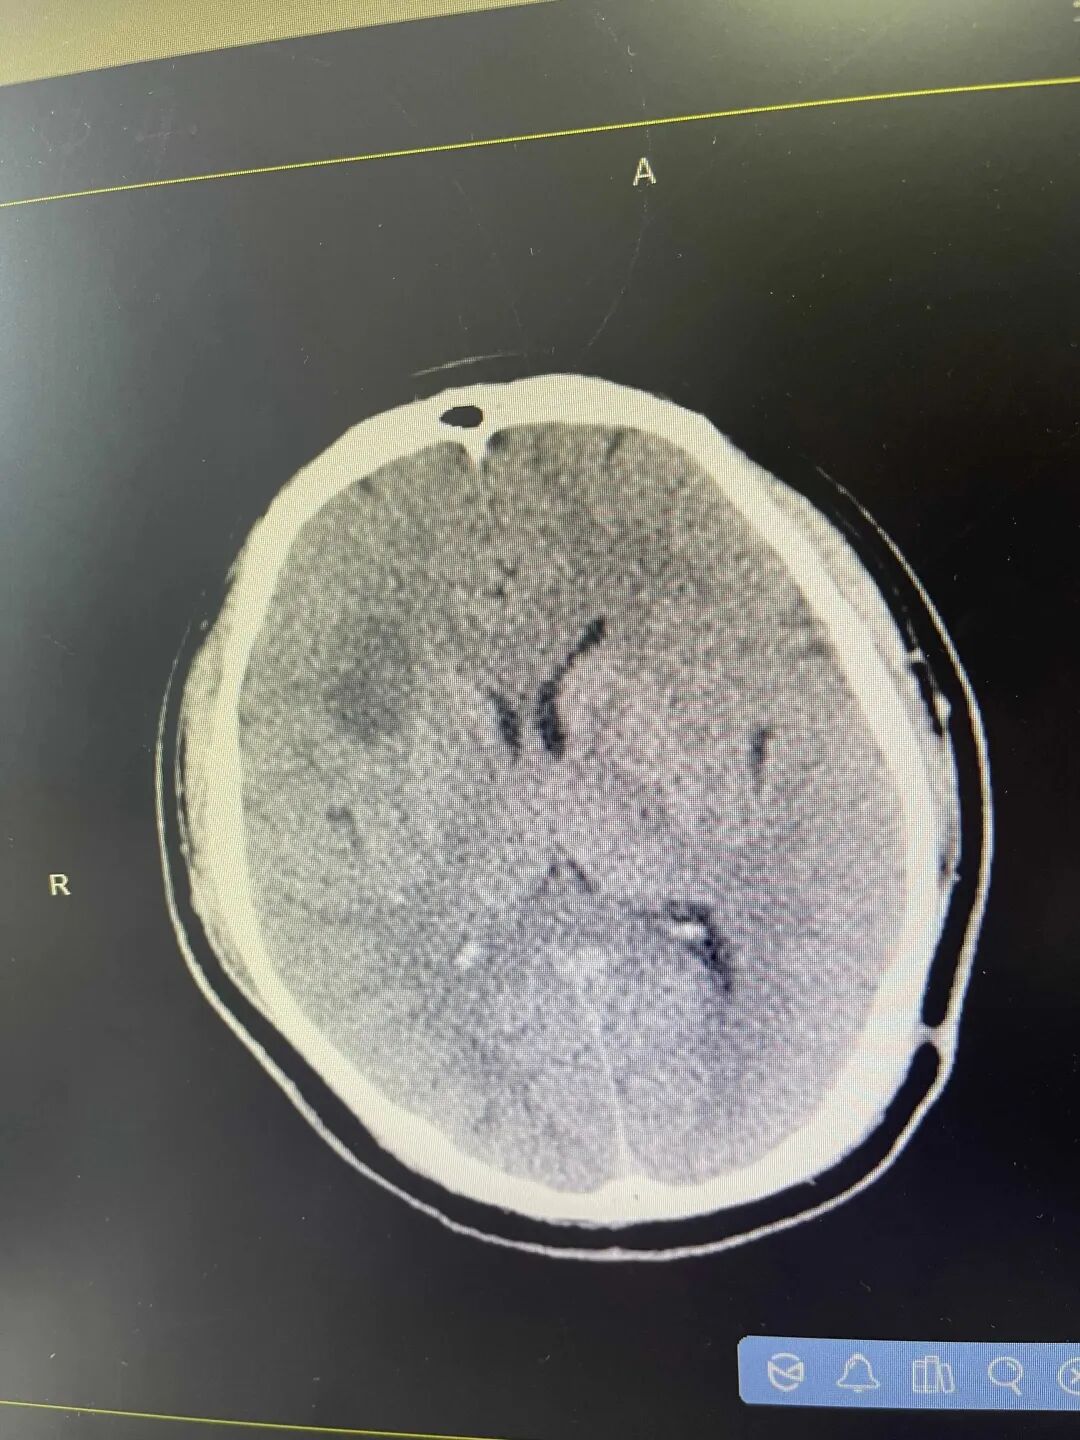

脑梗患者的影像图片,左上角深灰色区域提示脑梗。图片来源:宁波晚报